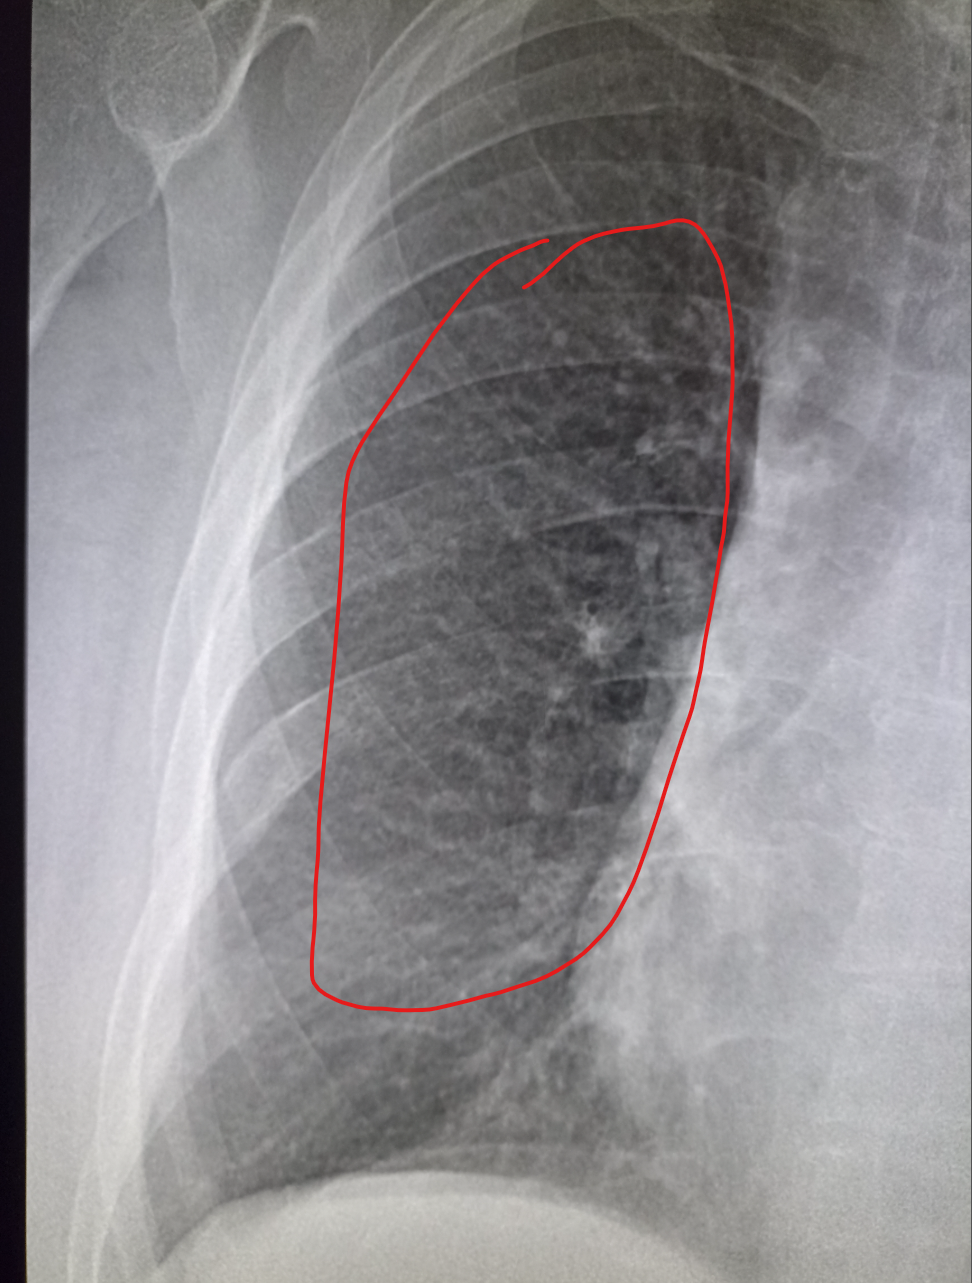

Здравствуй двачик, пишет вам простой рентгенолог из мухосранской поликлиники, сегодня я буду флексить зарплатой за ноябрь! Аж ПЯТЬДЕСЯТ ТРИ ТЫЩИ ПЕРЕВЕДУТ! С пруфом! А чего достигли вы? Ну и в доктора тож поиграем! Я буду вам картинки показывать, а вы пиздецомы находить! Найдите пиздецому на фтчк! Отчет еще по фог считать квартальный и годовой сегодня :-(